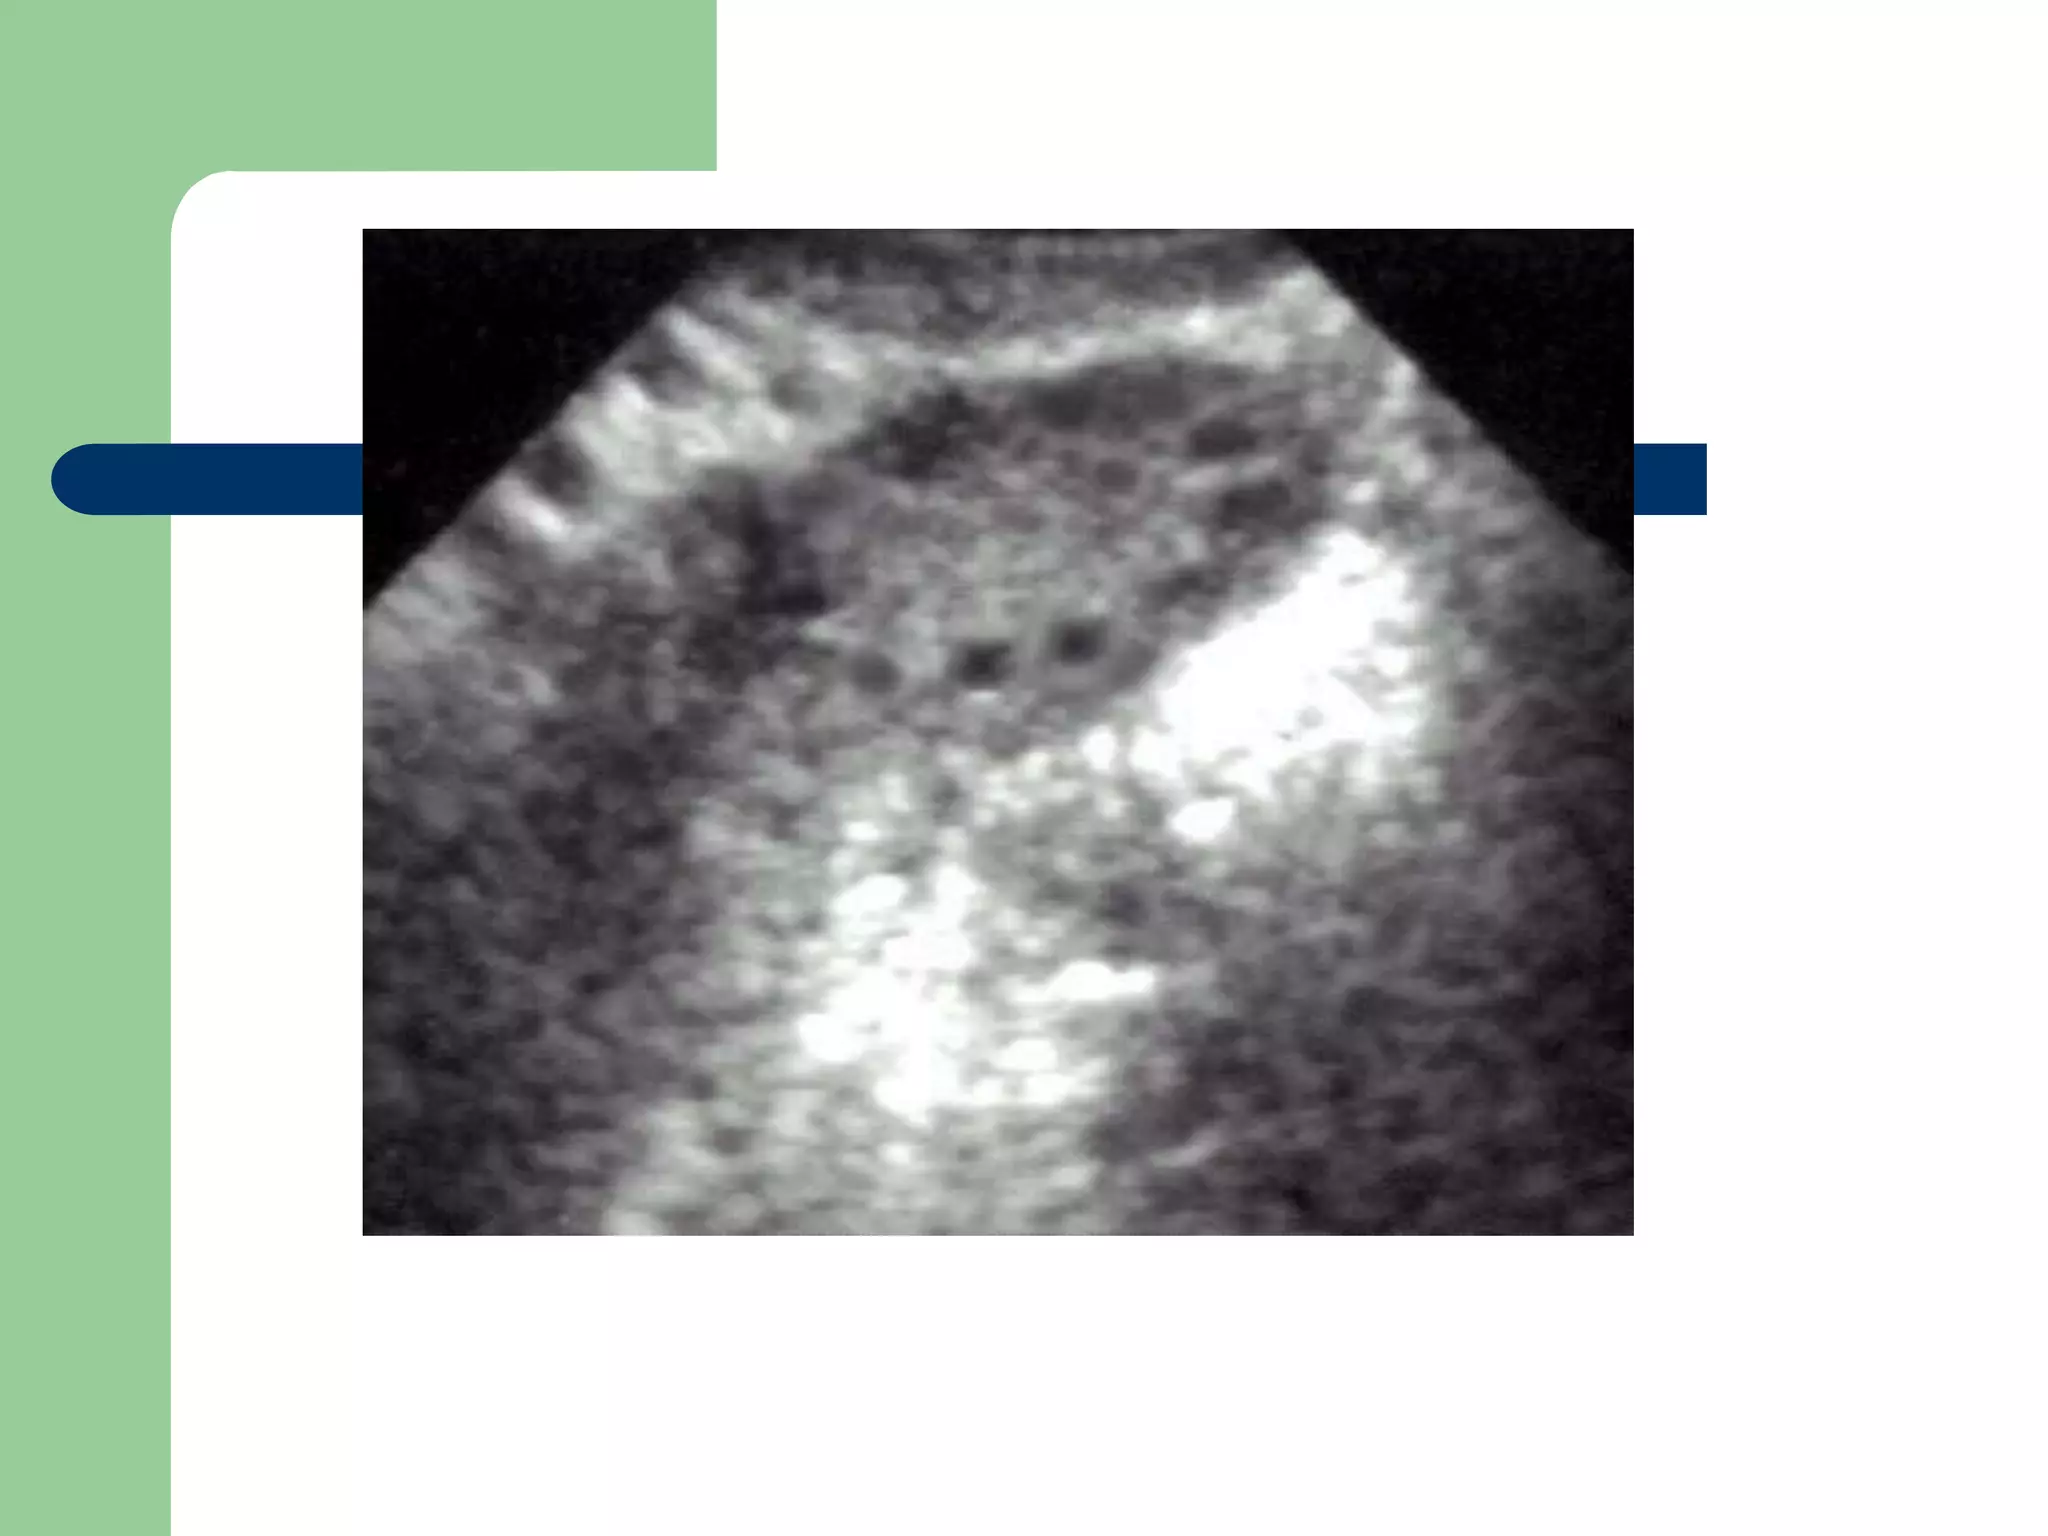

Pt presents with 6 week of amenorrhea and lower

abdominal pain (look at picture)

Qs

 What is the DD?

 What possible other symptoms?

 Give 4 risk factors.

 How would you treat?

 Ectopic pregnancy.

 PV bleeding, lower abdominal pain and

amenorrhea

 Previous Ectopic pregnancy

 Tubal disease

 Chronic PID and adhesions.

 Adhesions from endometriosis

 IUCD

 Tubal ligation

 How would you manage?

 Medical: methotrexate if it fits the

recommended criteria.

 Surgical: salpingostomy (if in ampulla and

uncomplicated) salpingectomy if otherwise

with checking the patency and health of the

other tube.